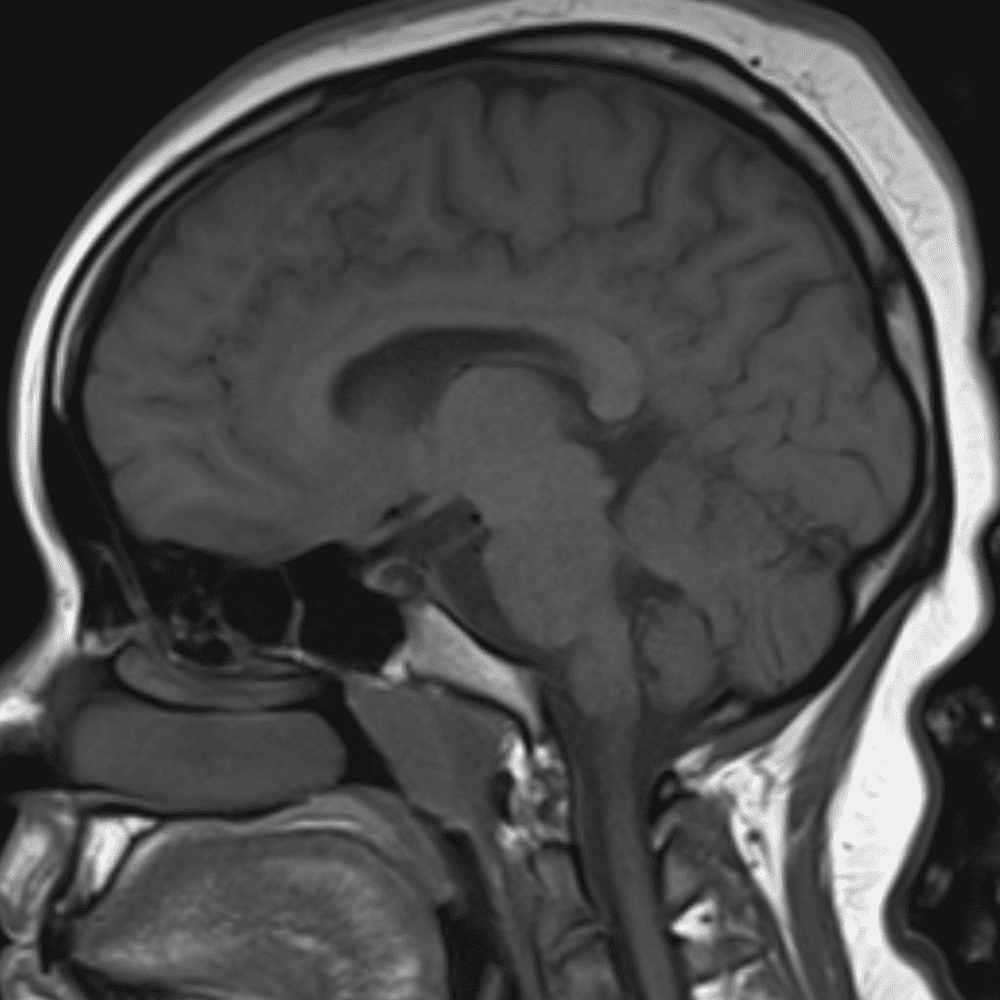

๋‹น์ง ์‹œ ํ”ํžˆ ๋ณผ ์ˆ˜ ์žˆ๋Š” ์‚ฌ๋ก€์˜ ์ „ํ˜•์ ์ธ ์˜ˆ๋ฅผ ํฌํ•จํ•ฉ๋‹ˆ๋‹ค.

39 ์‚ฌ๋ก€